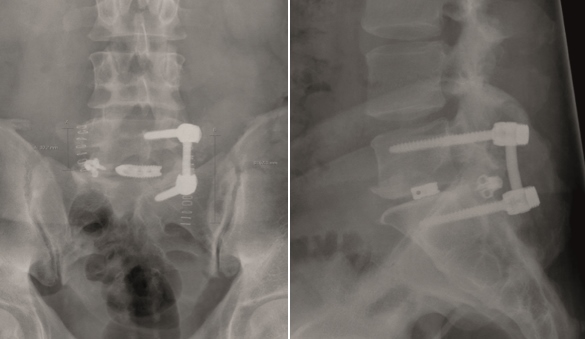

A 40-year-old man 5 years after ALIF L4-L5 using SynFix with axial low back pain. The CT scan shows locked pseudarthrosis (Fig 17). Nonoperative treatment failed. The treatment option was bilateral Facet Wedge at L4-L5.

A less invasive approach was used with Insight Retractor using the bilateral Facet Wedge. No bone graft. X-ray follow-up after 3 months and CT assessment after 6 months (Fig 18-19).